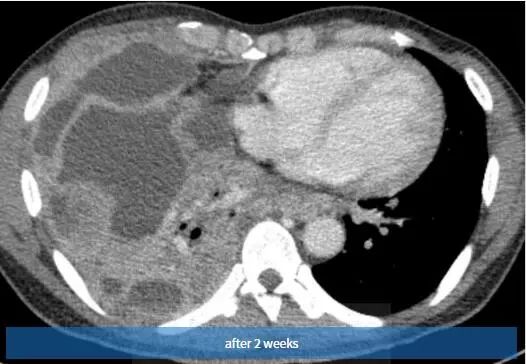

图3 2周后,随访胸片示右胸弥漫性阴影和胸腔积液。也可见引流管。

图4~6 2周内随访的对比增强轴位CT扫描示右半胸有大量多发性胸腔积液,弥漫性胸膜增厚和多灶性胸膜肿块。